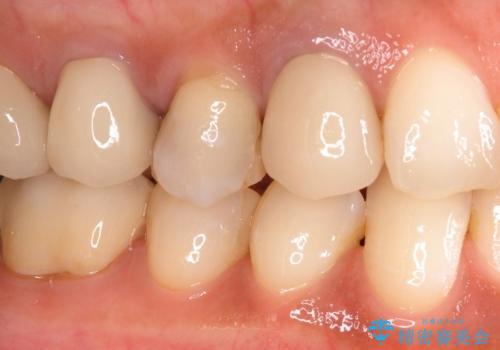

奥歯がしみる セラミックインレーによるむし歯治療

- 冷たいものがしみるとのことで来院された患者様です。

診査を行った結果、第一小臼歯にある樹脂の詰め物(コンポジットレジン)と歯の境目が痛みの原因であることが分かりました。

また、隣接する第二小臼歯も虫歯になっていることも分かったため、2歯を同時に治療するにしました。

下顎の目立つ位置であるため、セラミックインレーによる修復治療を行うこととしました。

精密に型取りを行ったセラミックインレーを装着したことで、治療後にはしみたり痛んだりという症状は治まりました。